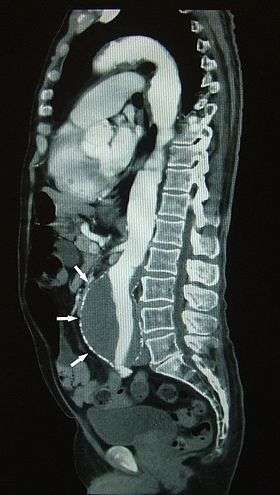

![]() Sagittal multiplanar reformation (SPR) of an abdominal aortic aneurysm (AAA) (arrows) | |

- Identify aneurysms in the aorta or in other major blood vessels. Aneurysms are diseased areas of a weakened blood vessel wall that bulges out—like a bulge in a tire. Aneurysms are life-threatening because they can rupture.